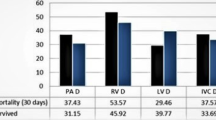

HUratio and HUdiff in patients with/without HF

HUratio (1.33 ± 0.34) and HUdiff (83 ± 79 HU) were significantly lower in patients without HF compared to patients with HF (HUratio 2.69 ± 1.44; HUdiff 250 ± 132 HU; both p < 0.001). Subdivision of HF patients into patients with preserved and reduced ejection fraction showed that HFratio and HFdiff were significantly higher in patients with HFrEF (HUratio: 3.19 ± 1.59, HUdiff: 291 ± 131) compared to HFpEF patients (HUratio: 1.99 ± 0.80, HUdiff: 192 ± 112, p < 0.001 and p = 0.006) and patients without HF (HUratio: 1.33 ± 0.34, HUdiff: 83 ± 79, both p < 0.001; Fig. 5).

Boxplots showing the highest HFratio (a) and HFdiff (b) in patients with HF and reduced left ventricular ejection fraction < 50% (HFrEF; HUratio: 3.19 ± 1.59, HUdiff: 291 ± 131) compared to HF patients with preserved left ventricular ejection fraction ≥ 50% (HFpEF; HUratio: 1.99 ± 0.80, HUdiff: 192 ± 112, p<0.001 and p = 0.006) and to patients without HF (HUratio: 1.33 ± 0.34, HUdiff: 83 ± 79, both p < 0.001)